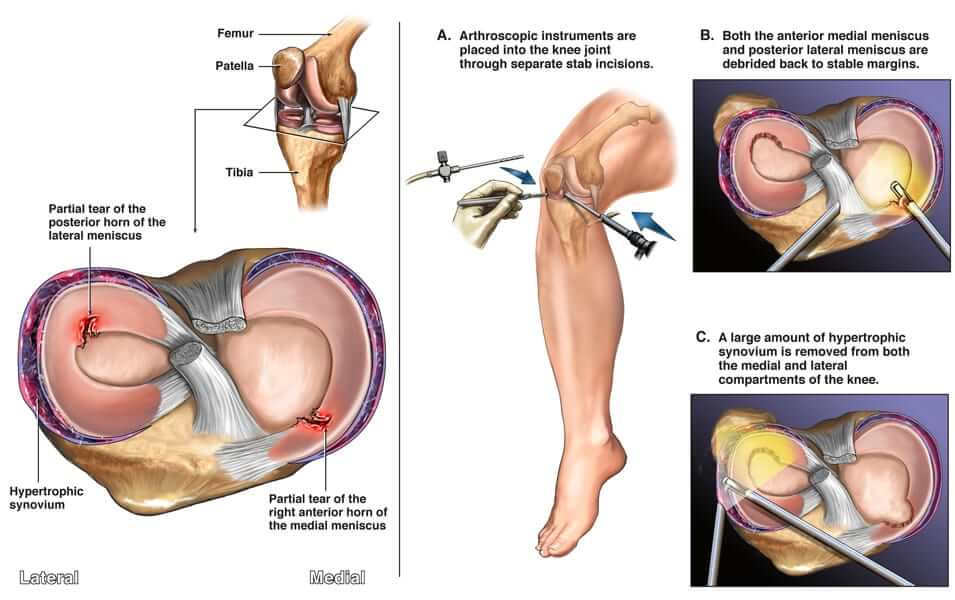

Artroskopik Menisküs Cerrahisinin Ortaya Çıkışı

1970’lerde artroskopik cerrahi, menisküs yırtıklarının tedavisinde devrim niteliğinde minimal invazif bir teknik olarak ortaya çıktı. Bu yaklaşım, küçük bir kameranın ve cerrahi aletlerin küçük kesilerden diz eklemine yerleştirilmesini içerir ve cerrahların deride büyük kesiler yapmadan yırtık menisküsü görüntülemesine ve onarmasına olanak tanır.

Artroskopik cerrahinin kullanılmaya başlanmasından bu yana menisküs onarım tekniklerinde önemli ilerlemeler kaydedilmiştir. İlk onarım teknikleri, menisküsün yırtık uçlarının tekrar bir araya dikilmesini içeren dikiş onarımına odaklanıyordu. Bununla birlikte, bu yaklaşımın karmaşık yırtıkları veya kan akışının daha az olduğu menisküsün periferik üçte birlik kısmını kapsayan yırtıkları ele alma yeteneği sınırlıydı.

Günümüzde menisküs yırtıklarının tedavisi yırtığın tipine, konumuna ve şiddetine göre değişmektedir. Küçük, stabil yırtıklar için dinlenme, buz, ağrı kesici ilaç ve fizik tedavi ile konservatif tedavi yeterli olabilir. Daha büyük veya daha karmaşık yırtıklar için artroskopik menisküs onarımı sıklıkla tercih edilen seçenektir. Menisküs onarımının mümkün olmadığı veya uygun olmadığı durumlarda kısmi menisektomi düşünülebilir. Diz ekleminin fonksiyonunu eski haline getirmek için seçilmiş vakalarda allograftlar ve otogreftler de kullanılır.